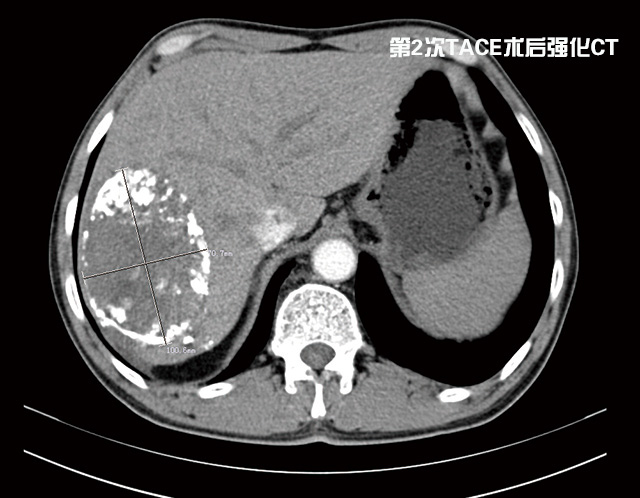

“這種情況不宜切除右半肝,因為左半肝體積小,余肝不能代償,切除后會導(dǎo)致肝功能衰竭,危及生命。必須先行介入治療,把供應(yīng)肝臟腫瘤的血管堵死, ‘餓死’癌細胞,使癌瘤縮小,左肝代償增大,待肝癌降期后再行手術(shù)治療,效果會比較好,也比較安全。”普外科首席專家李森主任分析說。期間劉大爺共經(jīng)過了2次介入治療,一個月前他來普外科復(fù)查時醫(yī)生告訴他腫瘤已明顯縮小,可以手術(shù),劉大爺心里一陣高興。

經(jīng)過充分準備后,由李森主任為他成功實施了肝第Ⅶ段、第Ⅵ段切除手術(shù),術(shù)后劉大爺恢復(fù)良好,精神抖擻,日前已康復(fù)出院。